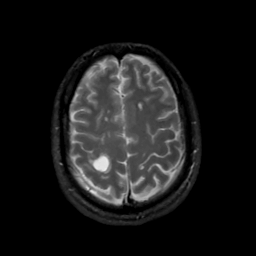

MR Study #4, March 3, 1991 -- Slice #39

[Home][Help][Clinical][Tour 1][Tour 2] Slice 39